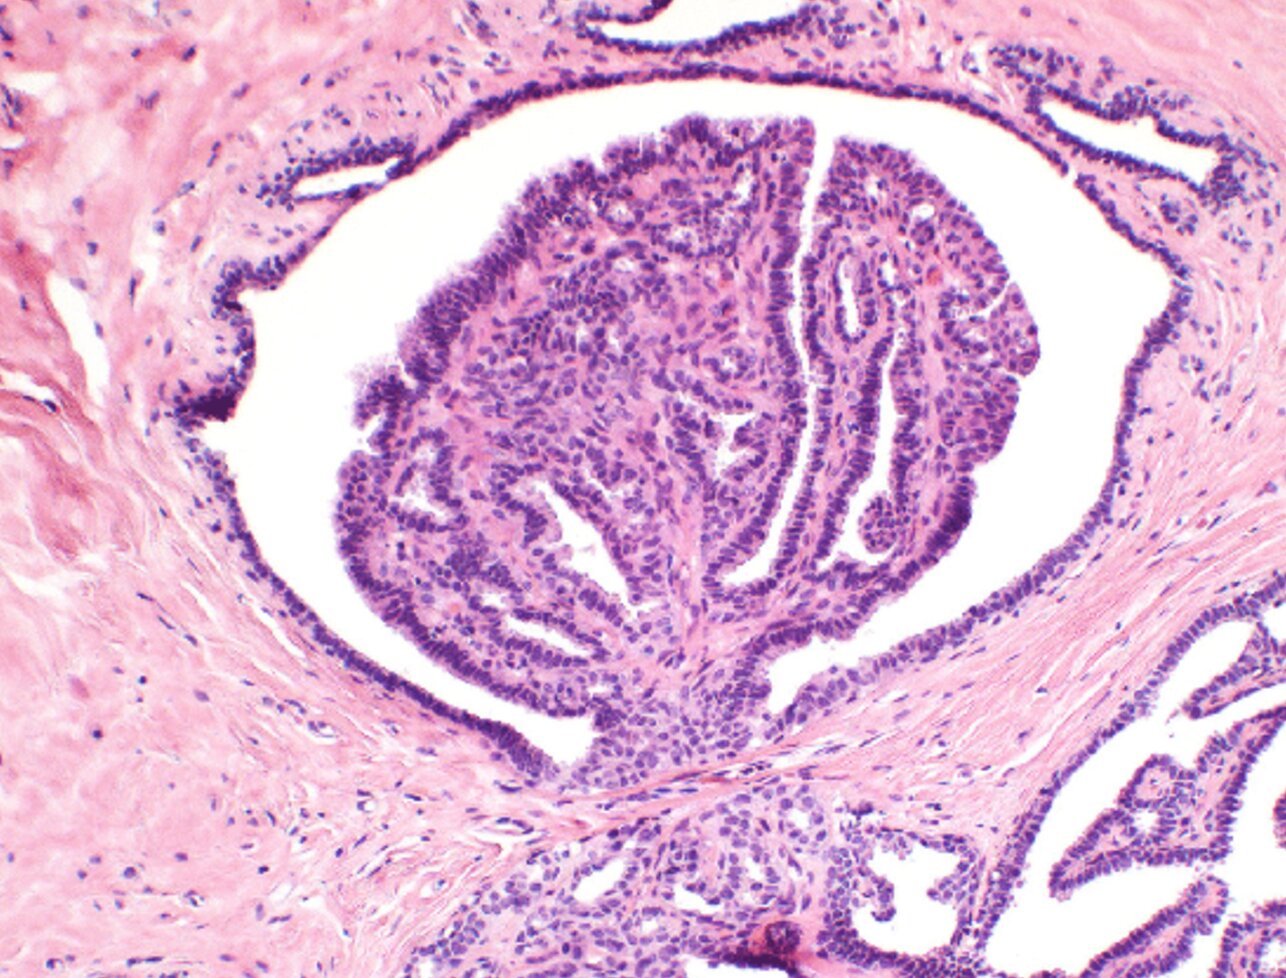

Einer unserer Schwerpunkte ist die Diagnostik von Erkrankungen der Brust. Wir sind spezialisiert auf die Begutachtung von Biopsien und Operationspräparaten der Mamma und bieten die vollständige morphologische und immunhistochemische Charakterisierung präinvasiver Läsionen und Mammakarzinome (einschliesslich prädiktiver Marker wie ER, PR, HER2, Ki67) an. Die Befundung erfolgt leitliniengerecht als Basis für operative und systemische Therapiekonzepte. Zur Qualitätssicherung legen wir hohen Wert auf Zweitbeurteilungen von Biopsien. Besondere Bedeutung hat die enge interdisziplinäre Zusammenarbeit mit klinischen Kollegen, um ein hohes Mass an Sicherheit und Qualität unserer Befunde zu erreichen. Unser Institut ist zertifizierter Kooperationspartner von mehreren Brustzentren.